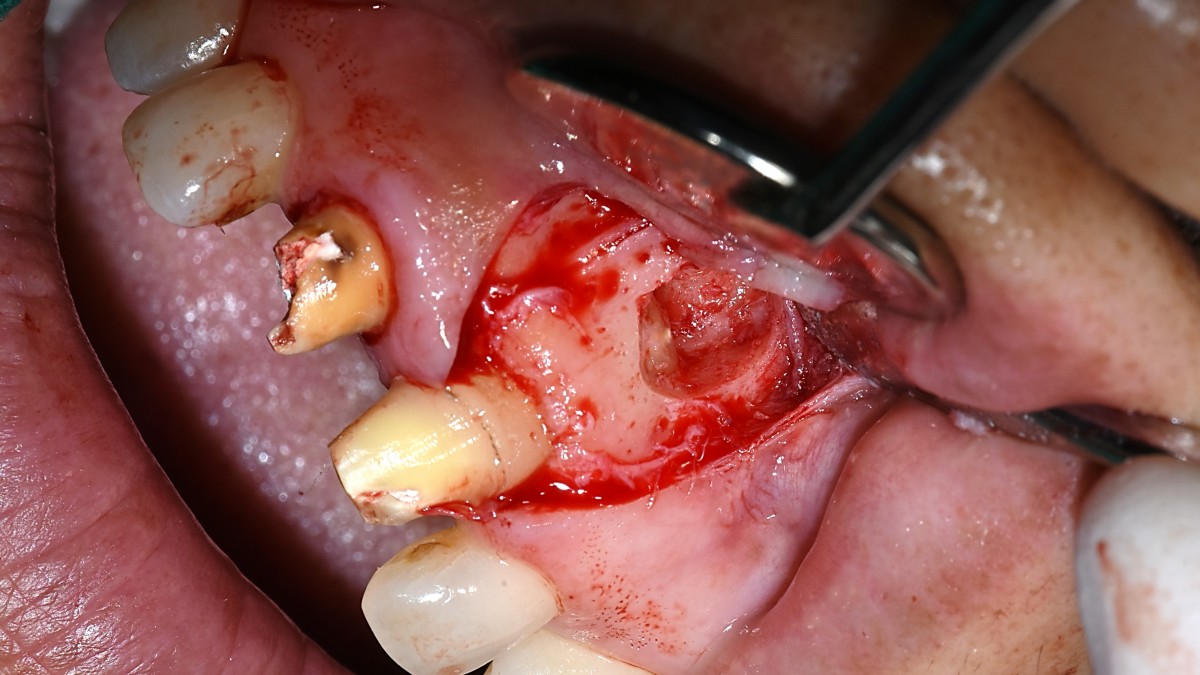

Apicorctomy /central incisor /GBR ; 6-year follow up.

<CJ SBN> Apicorctomy /central incisor /GBR ; 6-year follow up.